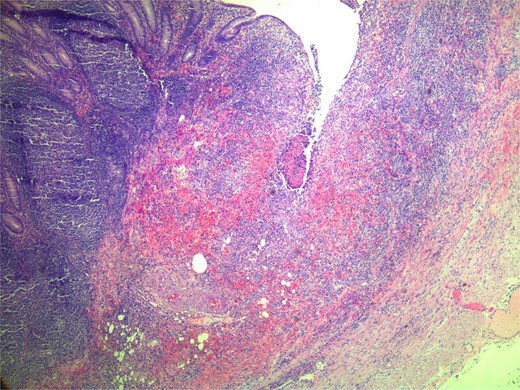

Macroscopic examination of the specimen demonstrated a clot-filled appendiceal lumen and a minimal increase in darkness in the submucosa. Microscopic examination demonstrated focal mucosal ulceration of 2 mm depth, with inflammatory infiltration extending to the muscularis propria, interstitial haemorrhage, and fibrosis (Figs 2 and 3). There was no eosinophilia or significant microscopic inflammatory exudate. This was deemed the most likely origin of bleeding with the final histological diagnosis of focal mild acute appendicitis with focal ulceration to submucosa (Fig. 1).

Microscopic zoomed in view of small ulceration measured to be 2 mm.